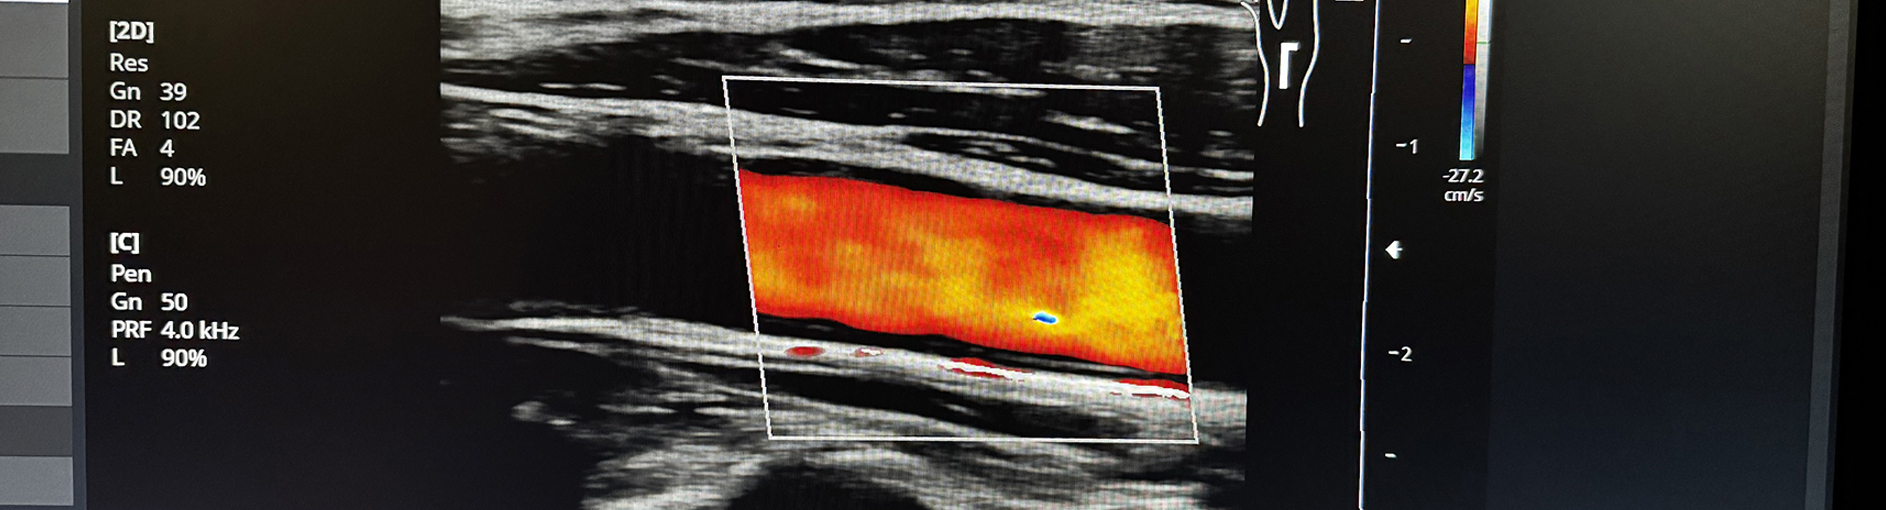

IgE-Laboranalyse 🩻 Farbultraschall

Hochauflösende Diagnostik ganz ohne Strahlenbelastung

Dr. Julia Lohmann verfügt über langjährige Erfahrung in der sonographischen Diagnostik.